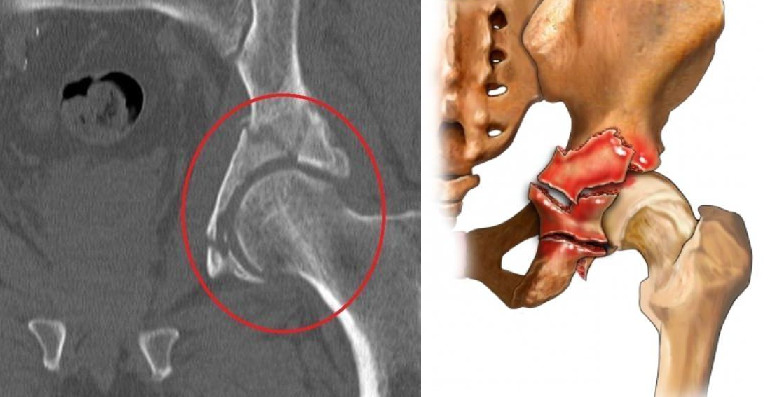

Переломы костных образований, формирующих впадину, наблюдаются после ДТП и прямых ударов в области сустава. Они могут сопровождаться переломами головки бедра или задней стенки вертлужного образования на тазовых костях. Для лечения подобных повреждений пациент нуждается в проведении скелетного вытяжения и хирургических вмешательств.

После перелома вертлужной впадины может возникнуть риск нарушения кровообращения в области бедра из-за повреждения сосудов или компрессии в результате отека или гематомы. Повреждение окружающих нервов в области бедра может привести к чувствительным нарушениям, параличам или другим неврологическим осложнениям.

Травмы таза и вертлужной впадины часто возникают в контексте политравмы и могут вызывать опасную для жизни гемодинамическую нестабильность. Понимание анатомии, физиологии и систем классификации поможет в оценке стабильности характера перелома и состояния пациента.